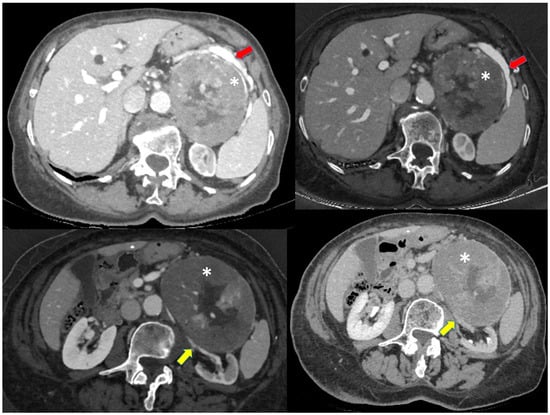

3. Case Presentation